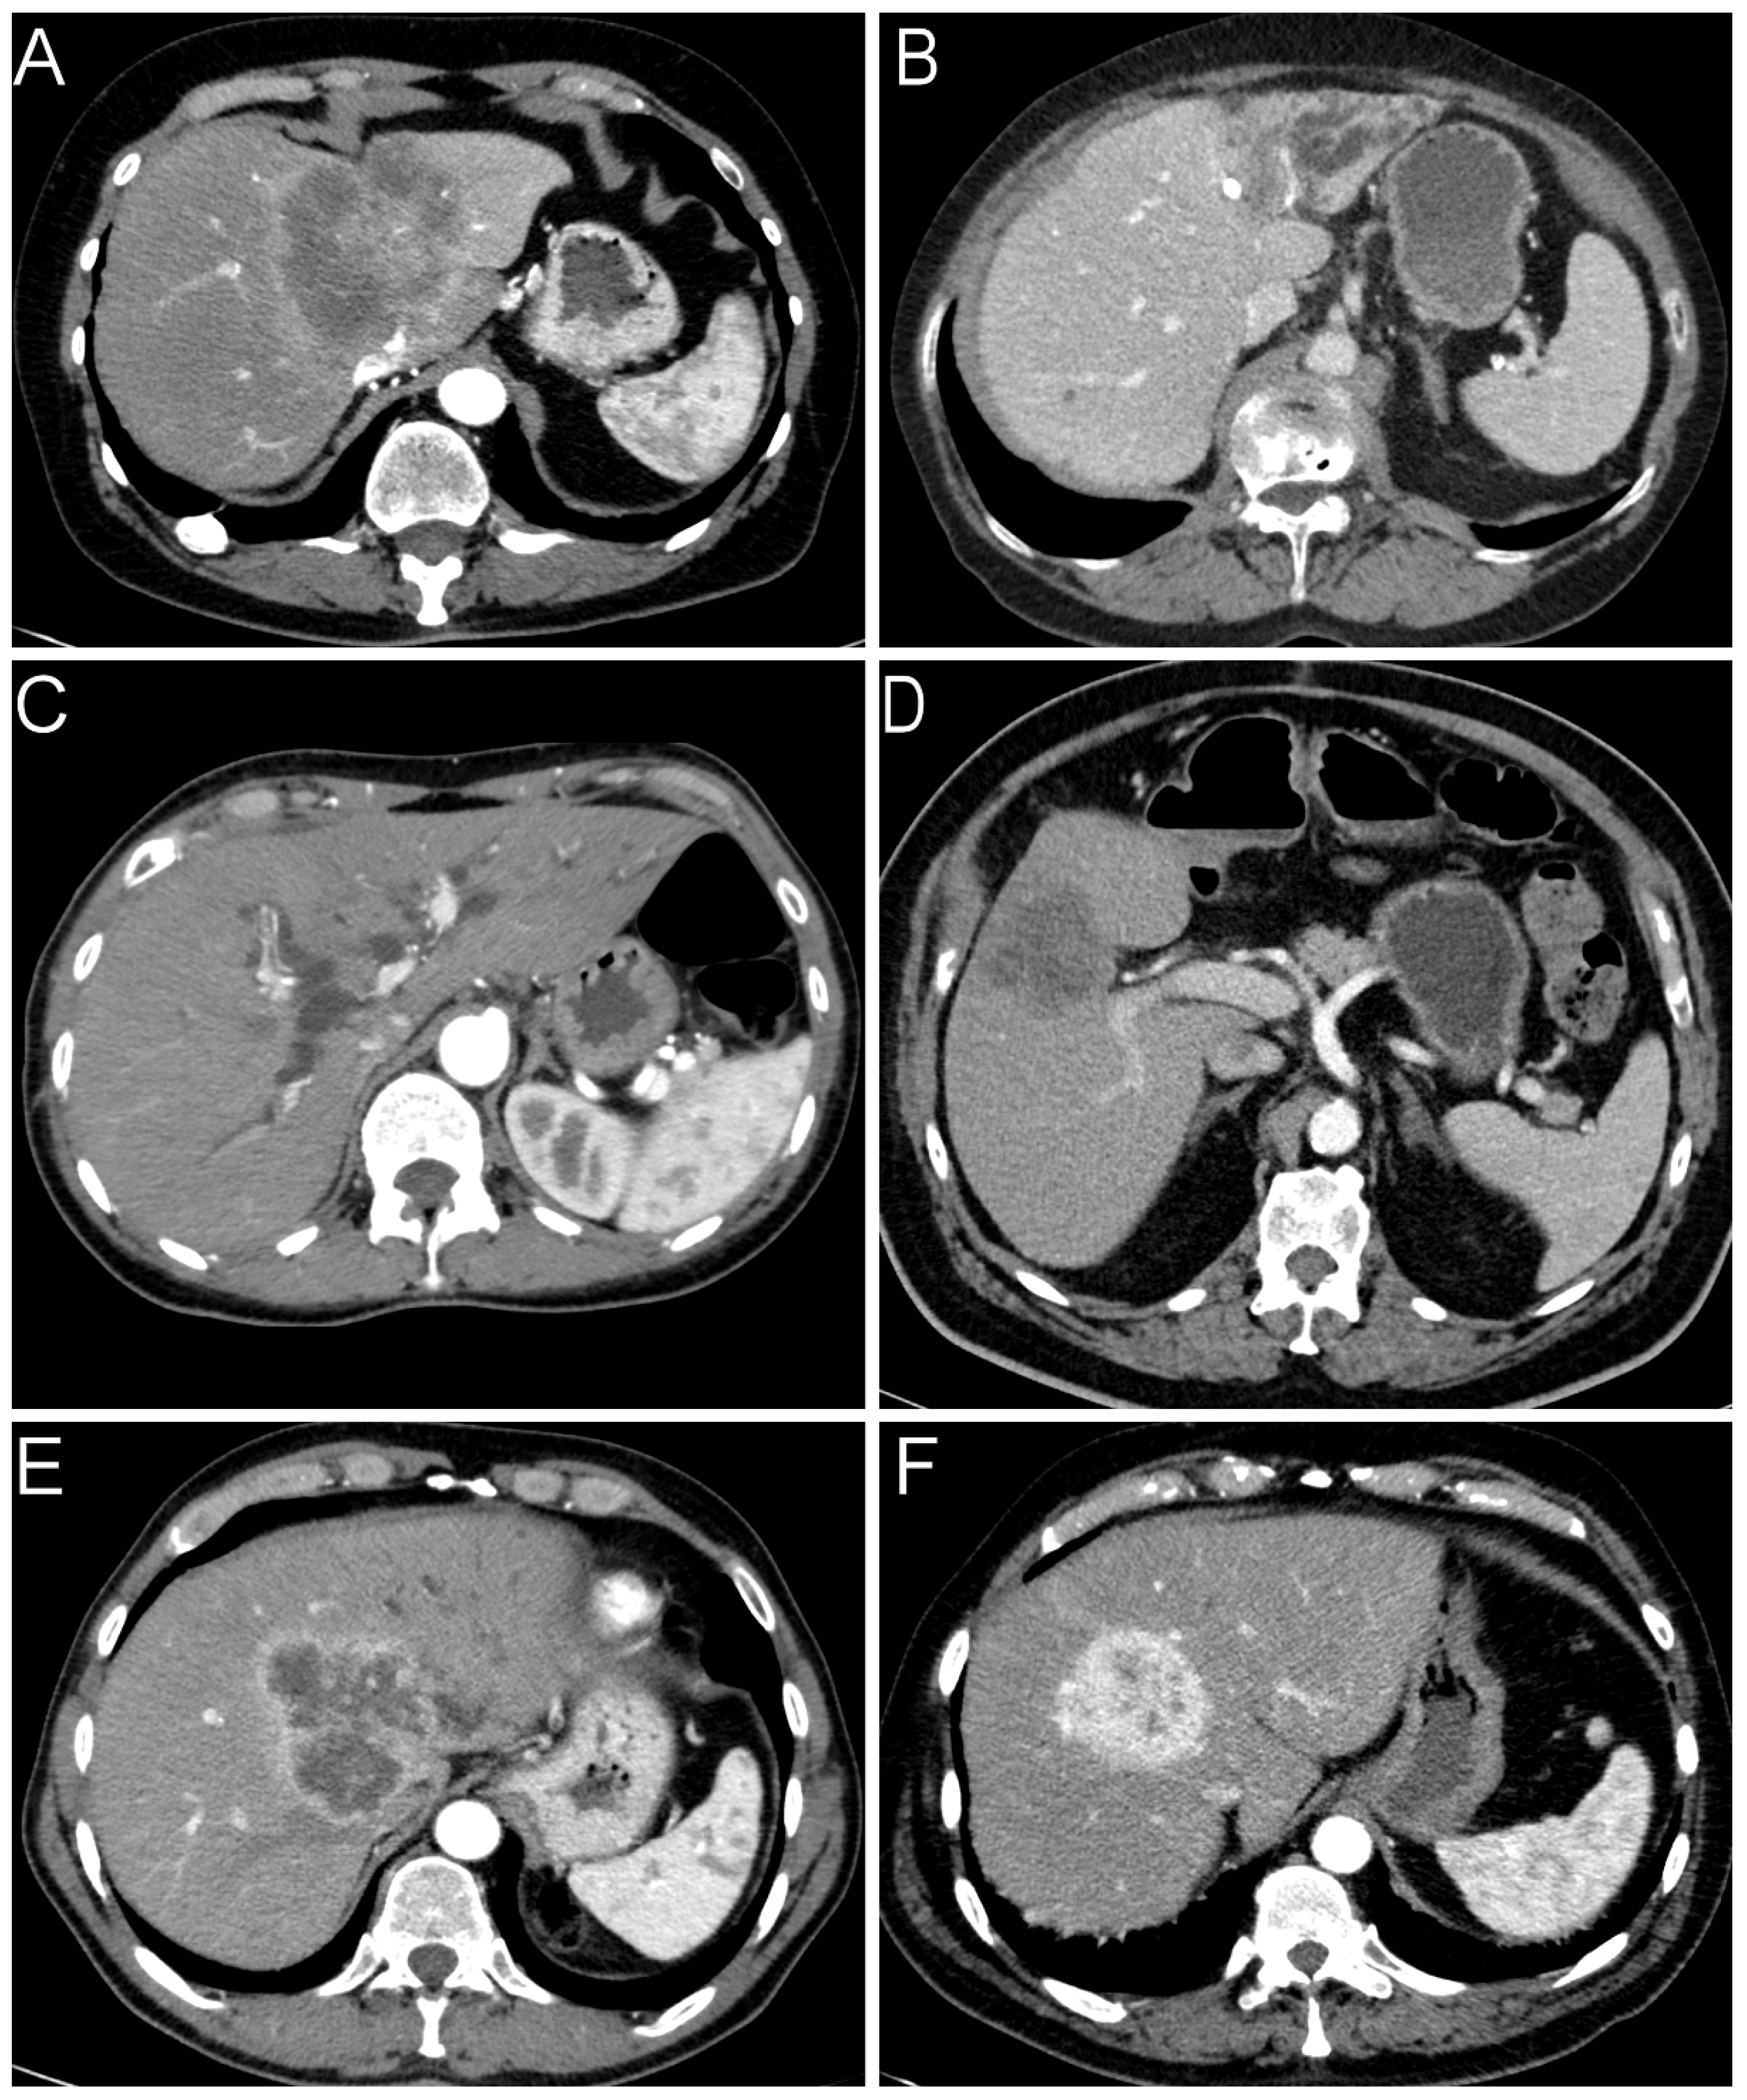

2.2. Radiological Findings

| Radiology | CT/ MRT [%] | 79/21 | 72/28 | |||||

| Tumor size [mean ± sd] | 7.79 ± 3.73 | 6.23 ± 2.30 | ||||||

| Ductal growing pattern [%] | 2 | 33 | <0.001 | 0.446 | <0.001 | 16.17 | 3.07–85.06 | |

| Obstruction bile ducts [%] | 25 | 48 | 0.001 | 0.237 | ||||

| Tumor density [mean ± sd] | 0.97 ± 0.34 | 0.91 ± 0.39 | ||||||

| Contrast agent behavior | ||||||||

| hypovascular [%] | 44 | 65 | 0.006 | 0.204 | ||||

| rim-enhanced [%] | 28 | 18 | 0.154 | |||||

| hypervascular [%] | 28 | 17 | 0.074 | |||||